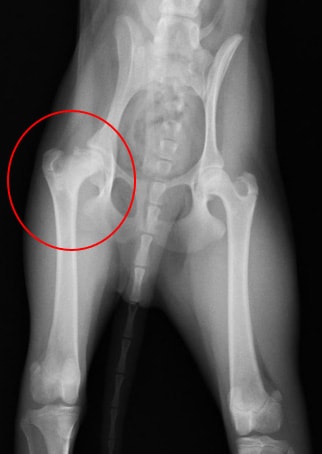

股関節脱臼① 関節包再建術とDeVitaピン法と伸縮性創外固定装置を併用して整復した一例

左の股関節が頭背側方向へ脱臼しているレントゲン写真です。 |